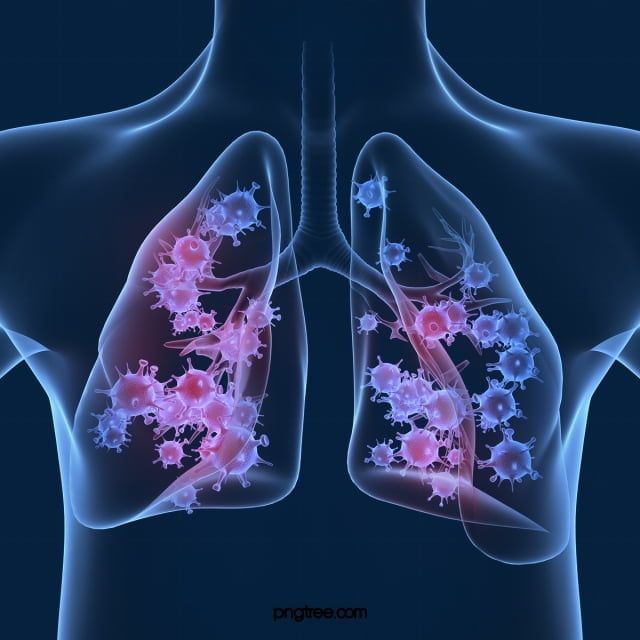

폐렴 증상 9. 입술이나 손끝이 푸르스름하게 변색 (청색증)

산소 포화도가 낮아지면서

입술, 손톱, 발끝이 보랏빛 또는 푸르스름하게 변하는 청색증이 생길 수 있습니다.

이는 폐렴이 상당히 진행된 상태일 수 있으므로 응급 상황입니다.10. 구토, 설사 등 소화기 증상